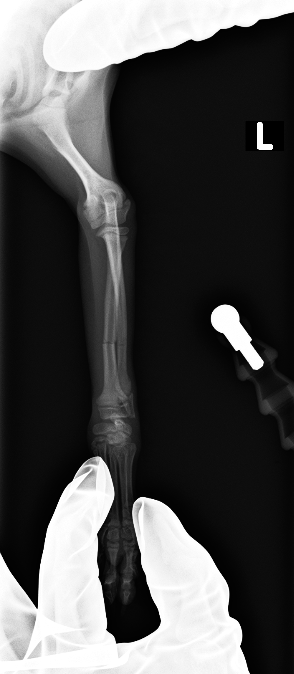

レントゲンより橈骨、尺骨の骨幹部で骨折が認められた

before